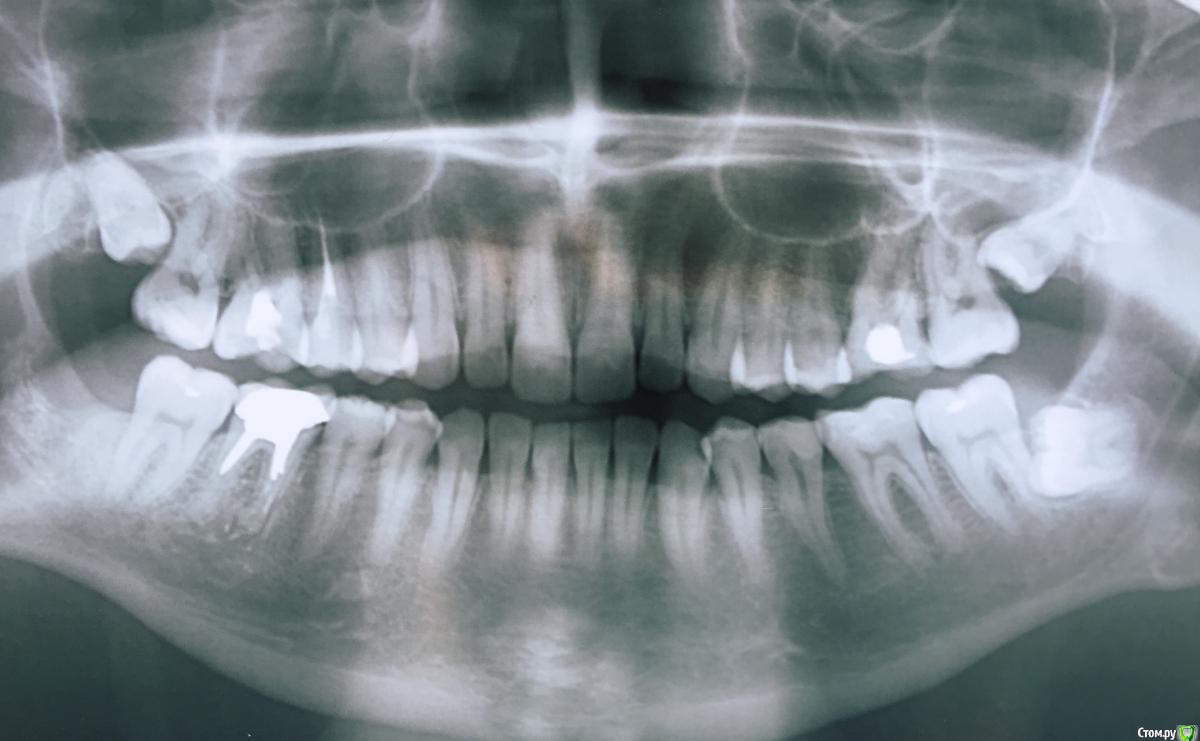

krq Опубликовано 20 мая, 2019 Поделиться Опубликовано 20 мая, 2019 (изменено) Здравствуйте. Прошло примерно пол года после удаления нижней 6ки. Сделал снимок более лучшего качества. https://i.imgur.com/aop8GMk.jpg 1. До этого были удалены 8ки, одна из которых лежала горизонтально. На том месте образовался какой-то рубец, сначала думал что это просто часть кости под десной, а сейчас на снимке заметил какую-то белую точку(это осколок?) Стоит ли что-то с этим делать? Я бы не сказал что он мешает, но если там надавливать, то будет не очень приятно, но я бы не назвал это болью.На фото с правой стороны.Еще если там водить языком, то иногда появляется какое-то странное ощущение как будто там исхудилась пломба. Но после планового перепломбирования соседней 7ки, ничего не поменялось. Хотя в последнее время стало проявляться реже после того как я как бы помассировал это место. 2. Что можете сказать по поводу 6ки. Могут ли быть какие-то осложнения при установке импланта. 3. На снимке видны какие-то кармашки на корнях зубов. Что это такое, начинающиеся воспаления? Снимок, примерно, полугодовалой давности из старой темы. Спасибо Изменено 20 мая, 2019 пользователем krq Ссылка на комментарий

red_butler Опубликовано 23 мая, 2019 Поделиться Опубликовано 23 мая, 2019 Стоит ли что-то с этим делать? нет Что можете сказать по поводу 6ки. Могут ли быть какие-то осложнения при установке импланта. при любом медицинском вмешательстве могут иметь место осложнения На снимке видны какие-то кармашки на корнях зубов. Что это такое, начинающиеся воспаления? периодонтит 1 Ссылка на комментарий

krq Опубликовано 23 мая, 2019 Автор Поделиться Опубликовано 23 мая, 2019 Спасибо за ответ периодонтит Почти на всех зубах? Вроде никаких проявлений нет. Приучил себя пользоваться нитью, внешне состояние зубов нормальное.Когда в последний раз был у стоматолога, он ничего не сказал, кроме того что нужно что-то делать с 6ми. Ссылка на комментарий